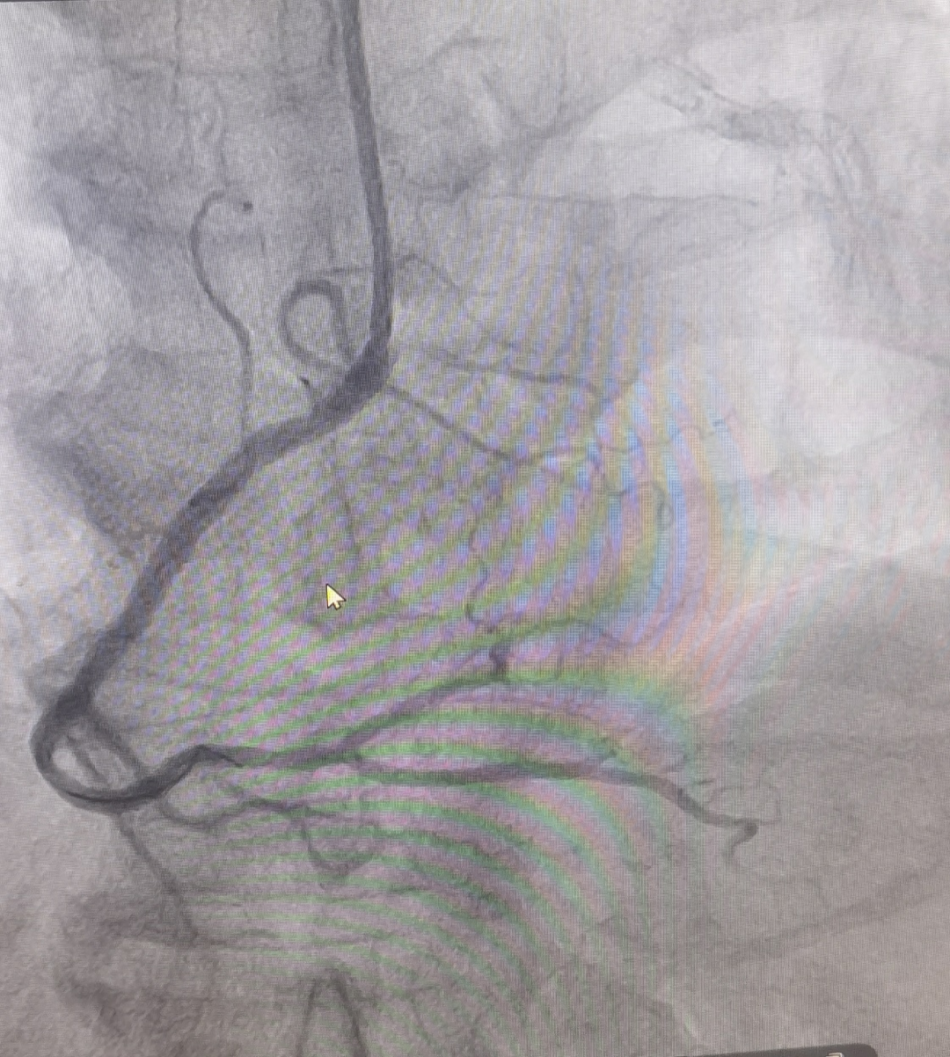

(圖為生物可吸收支架置入術后影像)

冠脈支架置入術歷史悠久,對冠脈重度狹窄患者效果確切。但是傳統支架一般都是金屬支架,置入后需長期服藥,并且支架一直保留在體內。隨著醫療技術的發展,生物可吸收支架是一項令人鼓舞的新技術,已初步表現出良好的治療效果和樂觀的應用前景,其獨具的可被完全降解吸收的特點,使支架本身能逐漸被人體組織吸收、降解、恢復靶血管的生物性,達到冠脈介入治療真正的“微創、無痕”的預期效果。另外,生物可吸收支架的置入避免金屬植入物永久存留體內的問題,對于年輕患者來說遠期效益更大。值得注意的是,為了達到更好的治療效果,術者應嚴格把握適應癥的選擇,同時在手術過程中要嚴格遵守PSP(充分預處理-選擇合適的支架尺寸-充分的后擴張)操作規程。